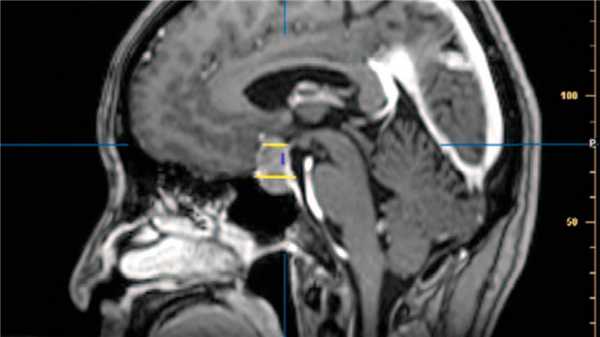

Гипофиз располагается в полости черепа, но этот момент стоит уточнить. Интересным здесь является то, что для гипофиза в клиновидной кости (одной из костей основания черепа) имеется специальное углубление. Это углубление носит название «турецкое седло». И действительно, визуально оно напоминает седло, у него даже есть хорошо выраженная спинка.

Орган располагается под головным мозгом, а если быть точным — под нижней его частью — гипоталамусом. Последний при этом связан с гипофизом посредством ножки, или гипофизарного стебля. Над гипофизом натянута мембрана, которая отделяет его от головного мозга. Таким образом, орган с одной стороны изолирован от образований головного мозга, а с другой стороны неразрывно связан с ними посредством ножки.

Прямо под турецким седлом, содержащим гипофиз, располагается клиновидная пазуха — полостное образование, которое граничит с полостью носа. Этот факт очень важен для нейрохирургов, поскольку позволяет осуществить оперативный доступ к гипофизу через нос. Именно таким способом в настоящее время проводят операции на органе.

Рисунок 1. Голова человека (схематически), вид сбоку. Пунктиром выделен гипофиз в турецком седле. Стрелкой показан хирургический доступ к железе через полость носа и клиновидную пазуху. Иллюстрация Данилы Мельникова

Рисунок 1. Расположение гипофиза в головном мозге. Источник: Patrick J. Lynch, medical illustrator / Wikipedia (CC BY-SA 3.0)